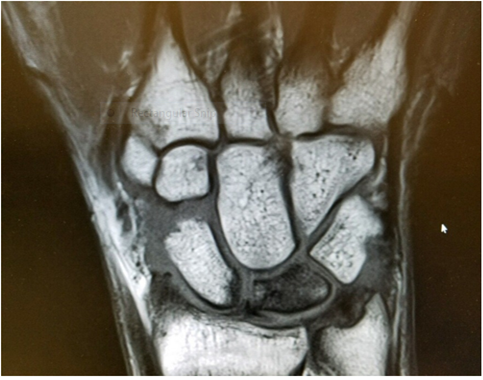

With documented failure of conservative treatment while returning to participation, the patient was referred to the team physician for further evaluation. Based off of the severity of the patient’s symptoms, the team physician ordered an MRI to assess for scapholunate dissociation. The MRI revealed the patient’s lunate had undergone a vascular necrosis consistent with KD (Figure 1). It was determined, in consultation with two additional hand surgeons, that the patient’s lunate was likely not salvageable. The prognoses for a non-surgical recovery, as well as surgical interventions were discussed with the patient. The patient elected to attempt non-operative treatment and rehabilitation with the athletic training staff in order to participate in his final season of competitive basketball.

Figure 1 Magnetic resonance image of the patient’s right wrist showing avascular necrosis of the lunate.